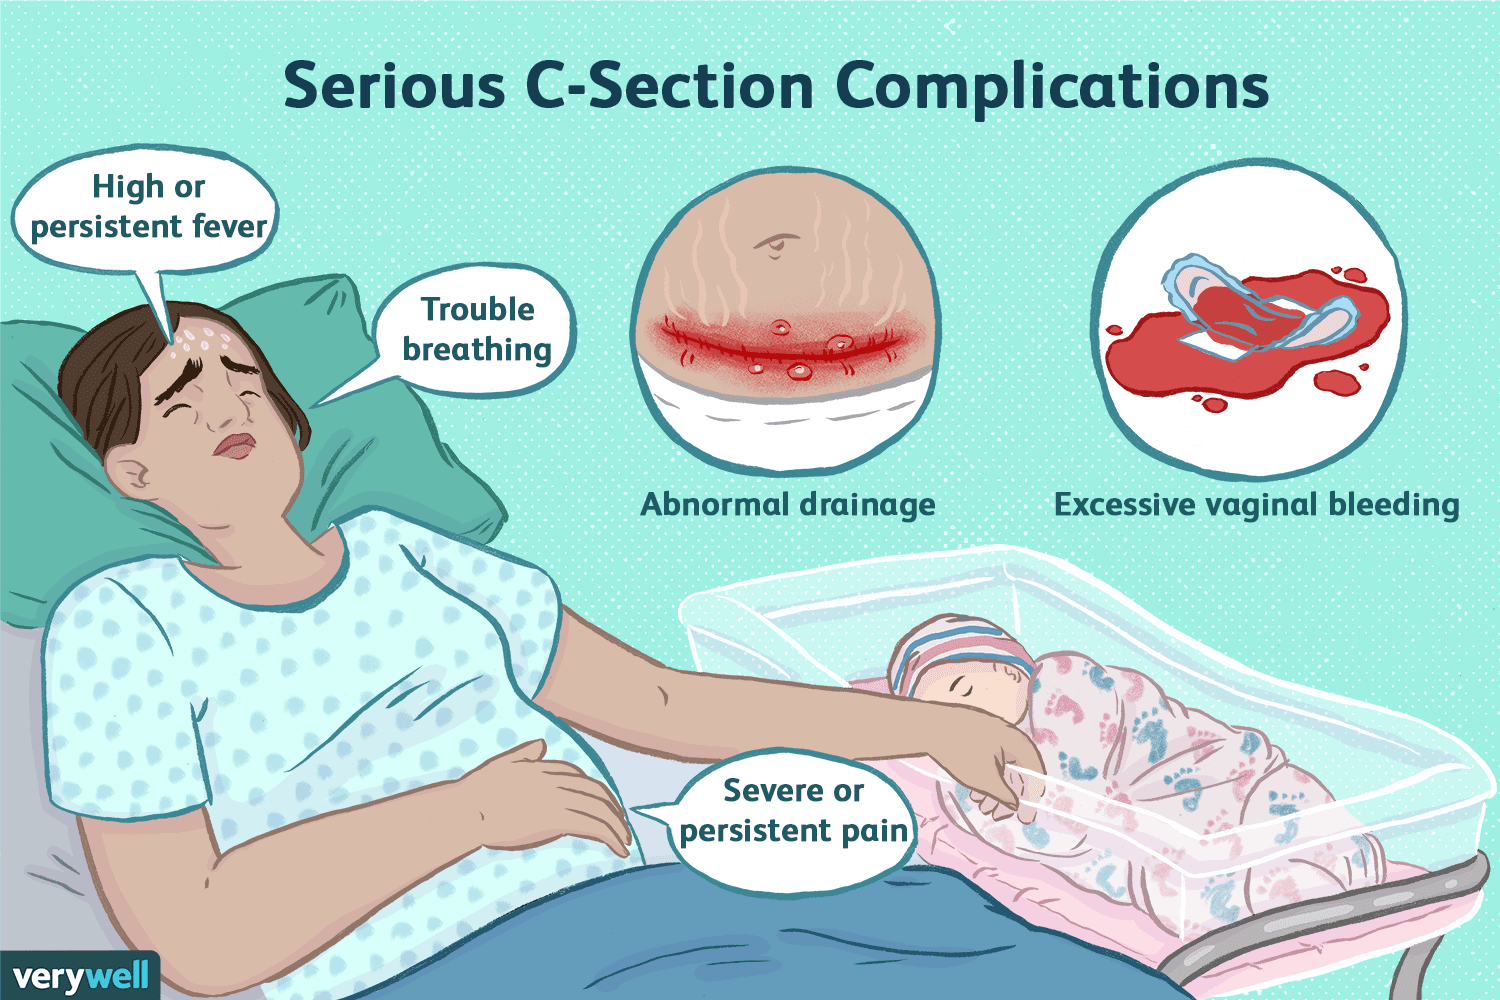

Dangers Of Getting Pregnant Soon After C Section

A Noninfectious infection After Cesarean Delivery

Cesarean Section Procedure Indications Risks And Complications